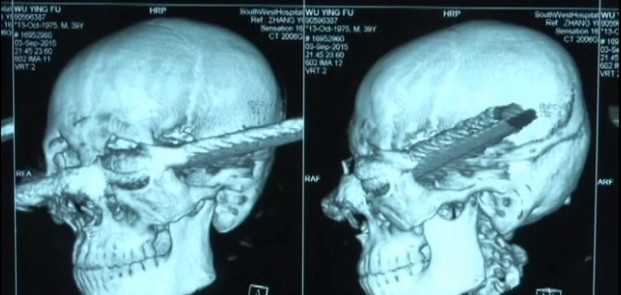

El milagro sucedió  en la provincia china de Chongqing, donde un obrero resbaló desde un andamio y cayó con su cabeza sobre una barra de metal de 30 centímetros.

La barra penetró por su ojo izquierdo y le llegó hasta el cráneo.

Ahora el trabajador se recupera de sus graves heridas, luego de ser sometido a nueve intervenciones quirúrgicas en Pekín y tras superar un estado de coma, informó RT.